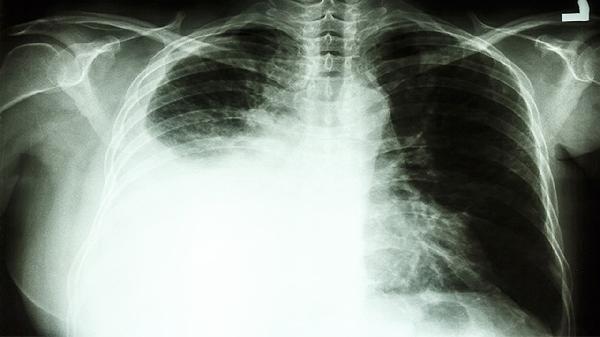

肺部CT检查对早期肺癌的检出率较高,尤其是低剂量螺旋CT可发现小至3毫米的结节。若半年前检查未见异常,说明当时肺部未出现达到检测阈值的占位性病变或组织结构异常。多数肺癌从细胞异变到形成可检测病灶需数年时间,短期内从无到有发展为临床期肺癌的概率较低。但需注意部分特殊类型肺癌如小细胞肺癌生长速度较快,或某些微小病灶因位置特殊未被检出。

存在持续咳嗽、痰中带血、胸痛等症状时,即使近期CT正常也应提高警惕。长期吸烟者、有肺癌家族史、接触石棉或放射性物质的高危人群,建议每年进行低剂量CT筛查。部分早期肺癌可能表现为磨玻璃样结节,这类病灶在初期容易被误判为炎症或漏诊,需要动态随访观察其变化。